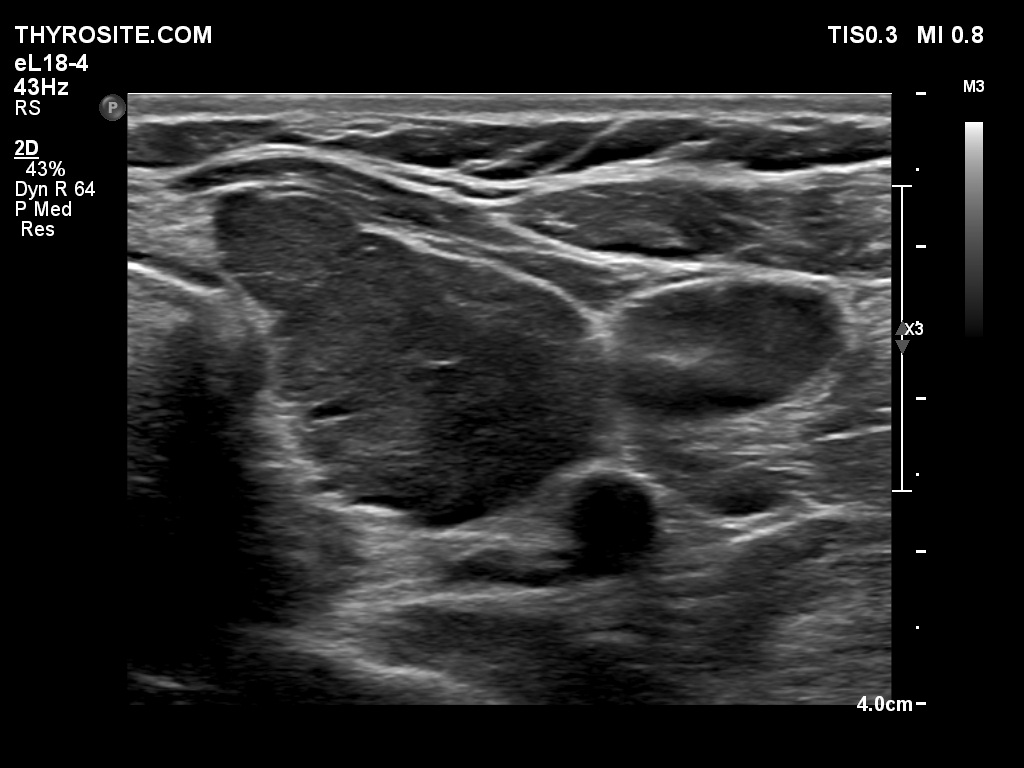

First examination - before surgery (first and second rows of images)

Clinical data: A 58-year-old woman with relapsing hyperthyroidism was managed by another team. She was sent for aspiration cytology. Multiple hypoechogenic nodules were described on ultrasonography.

Ultrasonography. Both lobes were hypoechogenic and contained several hypoechogenic areas do not corresponding to nodules. The echogenicity index was 20%. The vascularization was a bit increased.

Aspiration cytology was performed from one of the hypoechogenic areas in the right thyroid and resulted in benign, hormonal atypia.